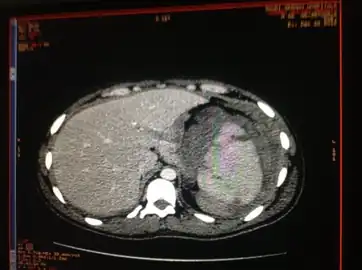

- Image of abdomen shows ruptured spleen (and the perisplenic hematoma)

- Traumatic rupture of the spleen on contrast enhanced axial CT (portal venous phase)

- Splenic hematoma resulting in free abdominal blood

Splenic rupture is usually evaluated by FAST ultrasound of the abdomen.[3] Generally this is not specific to splenic injury; however, it is useful to determine the presence of free floating blood in the peritoneum.[3] A diagnostic peritoneal lavage, while not ideal, may be used to evaluate the presence of internal bleeding a person who is hemodynamically unstable.[4] The FAST exam typically serves to evaluate the need to perform a CT scan.[4] Computed tomography with IV contrast is the preferred imaging study as it can provide high quality images of the full peritoneal cavity.[3]